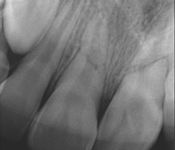

Pictured: Root Fractures/Splinting of Teeth and 1 Year Recall with Complete Root Formation

Parent of our 7-year-old patient was distraught by an injury that indicated horizontal root fractures in tooth #8 and tooth #9. Treatment involved splinting of teeth. After 1 year recall , the patient successfully had complete root formation.